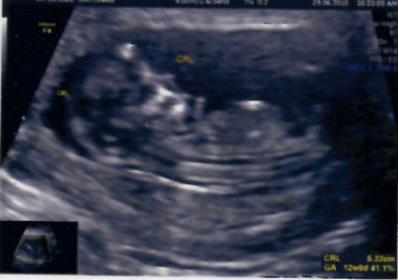

hi all,

Find attached clear images of 12W & 16 week as requeted. Pls let me know your predictions now.

Attachment 28310

Attachment 28311

Thanks! I think maybe a boy nub.